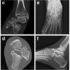

X-Ray

Plain radiographs are the simplest initial test during a suspected navicular fracture. Their sensitivity for identifying navicular fracture is low, however lateral and oblique radiographs provide the best chance of identifying a fracture. Rarely fractures of an adjunct navicular bone (if present) also are possible and should be visible.

CT

CT is more sensitive for identifying navicular fractures. It also allows for the assessment of the extent of the fracture line and therefore the degree of communication.